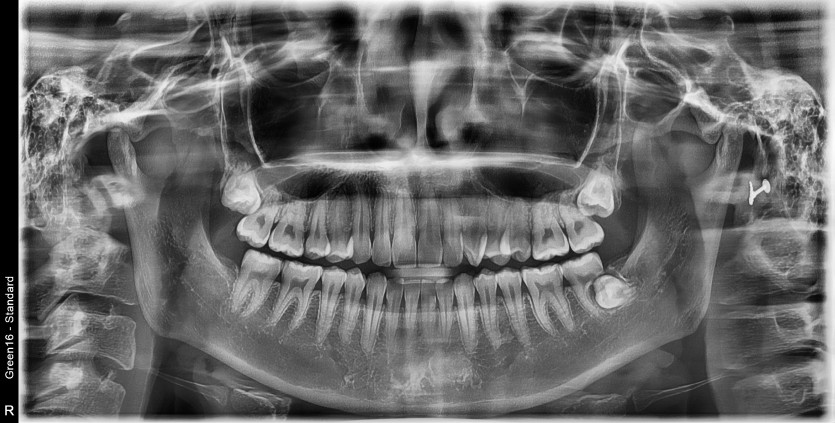

#38 사랑니 발치

구강 외과 전문의가 당일 발치 했습니다.